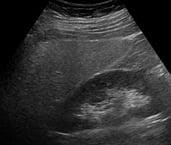

Più frequenza e certa è la diagnosi effettuata attraverso l’ecografia, un esame in cui si sfruttano le onde sonore per creare un’immagine degli organi interni.

Credit: By Hellerhoff – Own work, CC BY-SA 3.0, Link